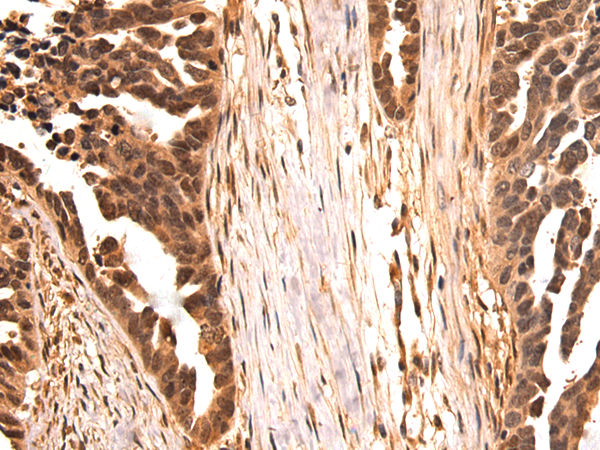

SPIN1 |

Synthesized peptide derived from internal of human SPIN1. |